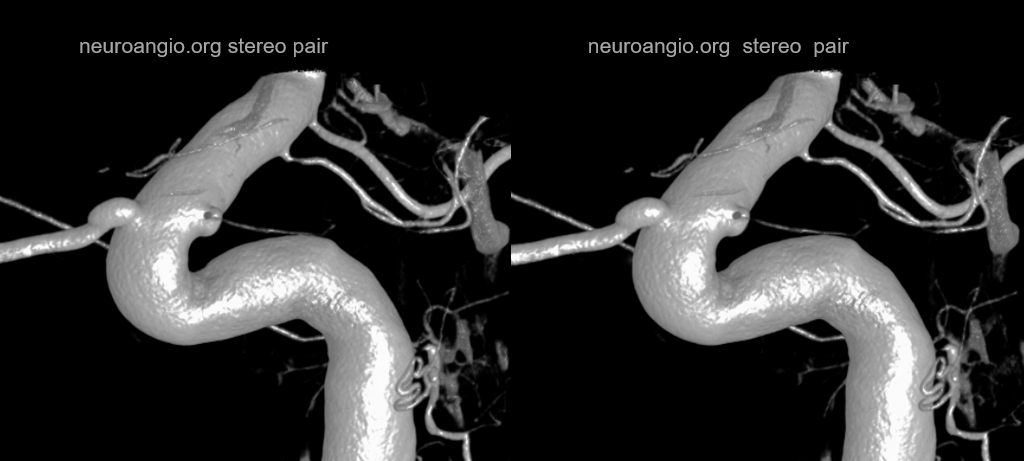

“Carotid Fenestration” — hypophyseal to PCOM connection

Super case by Dr. Eytan Raz

see that small branch to the anterior hypophysis?

ANOTHER EXAMPLE — Superior-Hypophyseal-PCOM Anastomosis

Lest you think these are super rare — well, probably its one in every 200 or so cases. We have seen 2 and did over 400 DYNAs of the area

This really begs the question of what is the embryologic relationship between the two — and how does that fit into the cranial/caudal ramus theory

MIP — superior hypophyseal – arrow; PCOM — dashed arrow; Anterior Choroidal — open arrow

Stereo VR

Axial MIPs. Same arrows. The anastomotic superior hypophyseal is the more distal one. There is another, more proximal superior hypophyseal (ball arrow) supplying the stalk